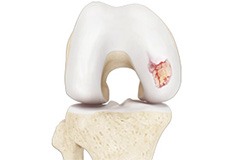

Osteochondral Defect of the Knee

An osteochondral defect, also commonly known as osteochondritis dissecans, of the knee refers to a damage or injury to the smooth articular cartilage surrounding the knee joint and the bone underneath the cartilage. The degree of damage may range from a rupture of the cartilage to a slight crack of the bone to a piece of the bone breaking off within the joint.